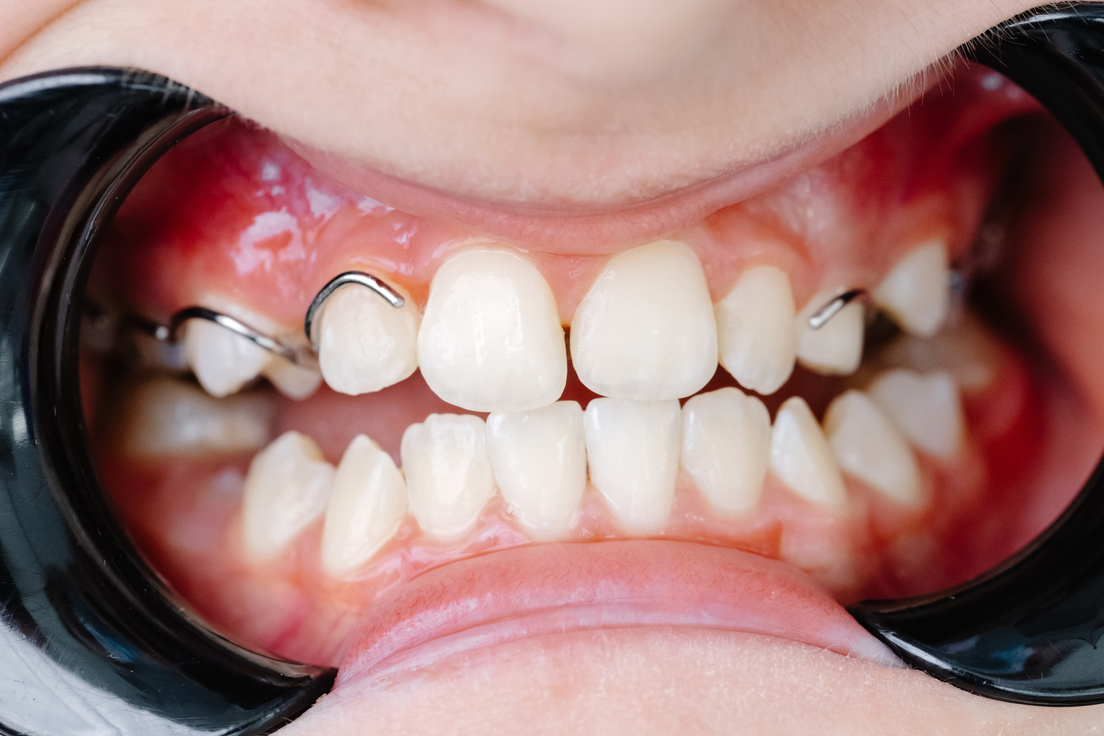

Los dientes son como piezas de un rompecabezas que deben encajar de cierta forma entre sí, como si formasen una cremallera. Grosso modo, no debe haber piezas dentales apiñadas o excesivamente separadas, y los dientes superiores deben superponerse ligeramente por delante de los inferiores, mientras que los laterales estar en estrecho contacto. Esto garantiza una masticación efectiva y eficiente.

En caso contrario, cuando los dientes y la mandíbula no encajan correctamente al morder —en lo que se conoce como desalineación dental o maloclusión— las consecuencias no son solo estéticas como la mayoría de las personas cree. Desafortunadamente, muchos no ven la necesidad de corregir esta situación o acuden tarde, sin saber que sus efectos pueden extenderse.

La ortodoncia es uno de los tratamientos más comunes en caso de una mordida imperfecta. Hoy en día, las opciones, tanto en materiales como en métodos, son más diversas que en el pasado y dependen del tipo y gravedad de la maloclusión, así como de otros factores individuales. Los apliques dentales o 'brackets', así como los alineadores, son una solución de eficacia comprobada. Ambos ejercen una presión gradual sobre los dientes, moviéndolos hacia una posición adecuada.